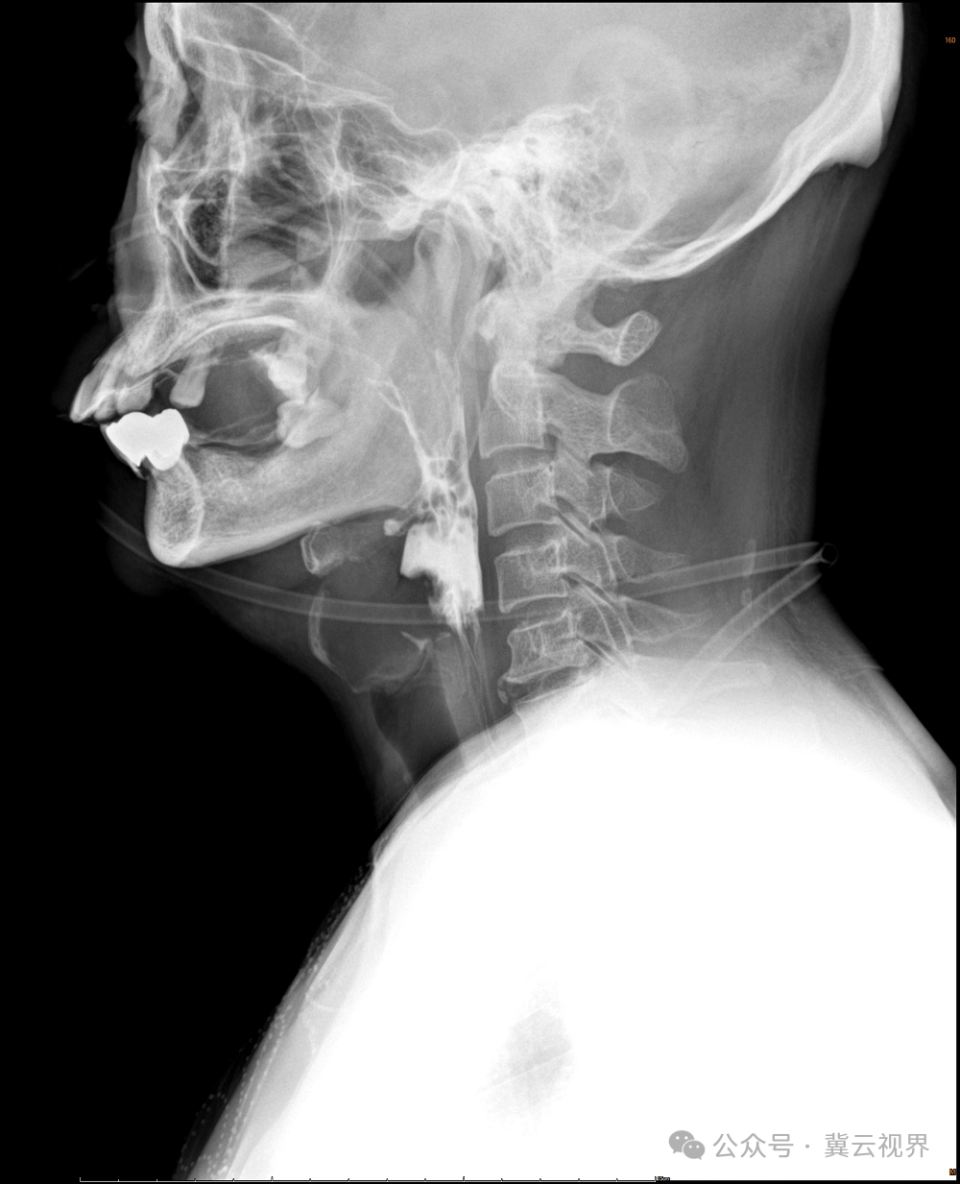

口腔、咽部造影剂填充动态影像

1.直观清晰,洞察真相。在X线清晰映照下,治疗师能像亲眼所见一样,仔细观察患者进食时整个吞咽过程的运动情况。吞咽动作是否异常、食物残留位置,都能一目了然。这有助于明确吞咽障碍发生的具体阶段和根本原因,为医生提供精准的诊断依据。